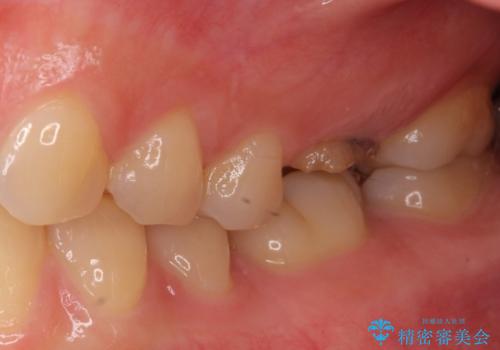

抜歯の上インプラントによる補綴治療を行うこととなりましたが、前歯の叢生も気になるとのことで並行して矯正治療を行うこととしました。

歯列不正は軽微であったので、インビザラインによる矯正治療とし、矯正治療中にインプラント埋入を行う予定としました。

前歯のデコボコも解消され、ブラッシングが楽になりました。